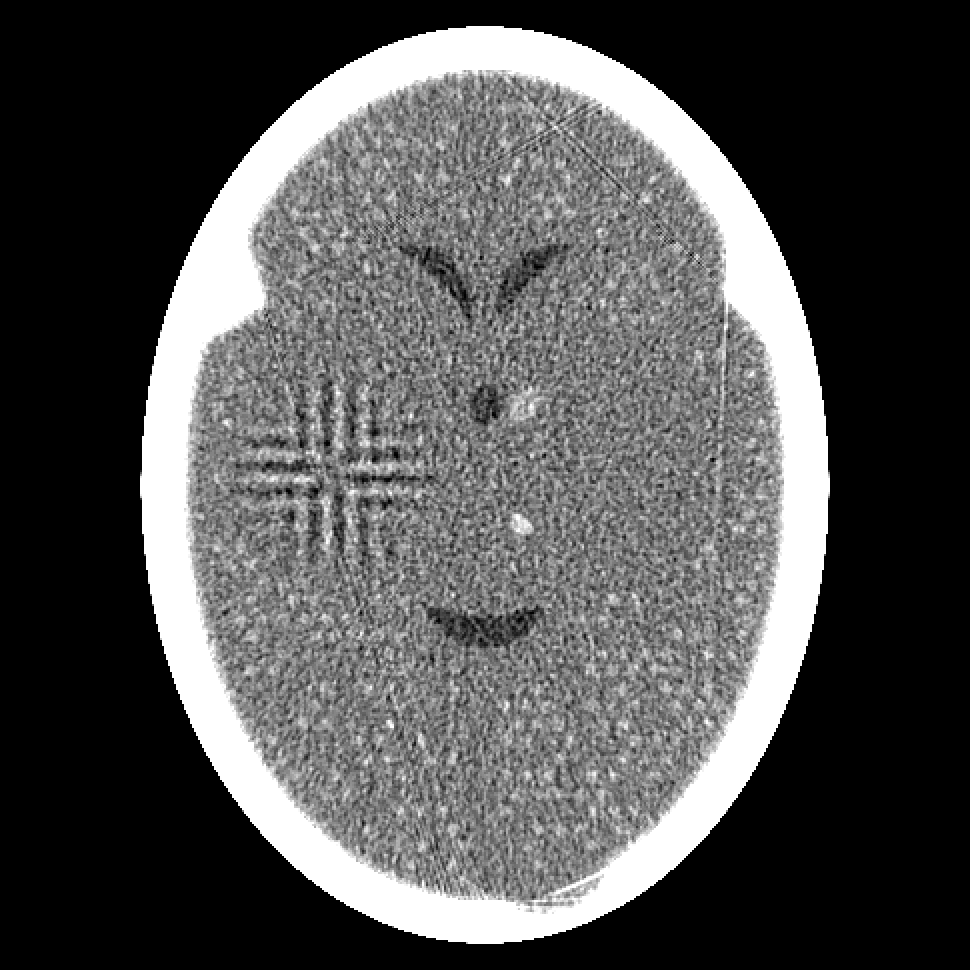

Figure 4: Reconstructions from 720 projections by (a) filtered back-projection, (b) the algorithm ART, (c) TV-Based Superiorized Version of ART, and (d) Shearlet-Based Superiorized Version of ART.

For this anecdotal experiment we use three different numbers of views (i.e., projections): 180, 360, and 720. We emphasize that, in the currently-described anecdotal experiment, there is only one phantom (which provides the ground truth); random generation of local inhomogeneities and of tumor locations is done only once and the same arrangement of local inhomogeneities and of tumor locations is used when generating the projection data for the three different numbers of views.

We present the visual results of the reconstructions produced by these algorithms when using 180, 360, and 720 projections in Figures 2, 3, and 4, respectively. We now give our impressions based on these visual results.

As expected, the greater are the number of projections, the better are the reconstructions produced by any of the four algorithms. However, even with 720 projections, the reconstruction produced by the Shearlet-Based Superiorized Version of ART still shows some high-frequency artifacts and the small tumors are less visible than in the images produced by the other three algorithms.